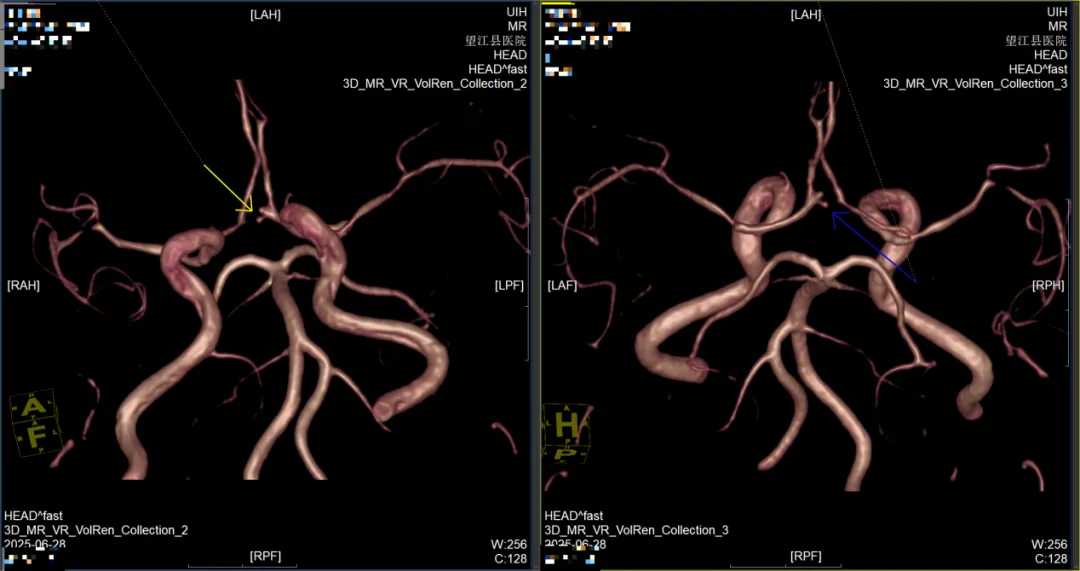

1.MRA(磁共振血管成像):揪出腦內(nèi)“隱形炸彈”——小動脈瘤;顱內(nèi)動脈瘤破裂是導(dǎo)致猝死性蛛網(wǎng)膜下腔出血的首要原因,而多數(shù)患者在破裂前毫無癥狀。傳統(tǒng)檢查容易漏診<3mm的小動脈瘤,但MRA無需注射造影劑即可清晰顯示血管三維結(jié)構(gòu),靈敏度高達(dá)95%,能精準(zhǔn)識別微小動脈瘤的位置、形態(tài)和血流動力學(xué)特征,為后續(xù)干預(yù)提供關(guān)鍵依據(jù)。

前交通動脈瘤